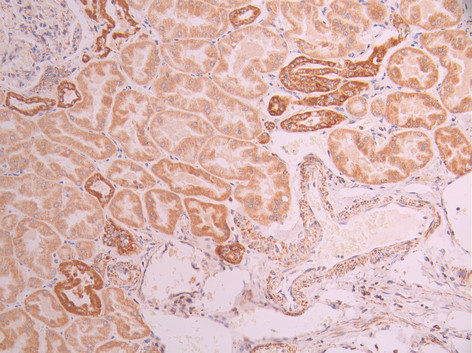

IHC image of CSB-RA092384A0HU diluted at 1:100 and staining in paraffin-embedded human kidney tissue performed on a Leica BondTM system. After dewaxing and hydration, antigen retrieval was mediated by high pressure in a citrate buffer (pH 6.0). Section was blocked with 10% normal goat serum 30min at RT. Then primary antibody (1% BSA) was incubated at 4°C overnight. The primary is detected by a Goat anti-rabbit polymer IgG labeled by HRP and visualized using 0.05% DAB.